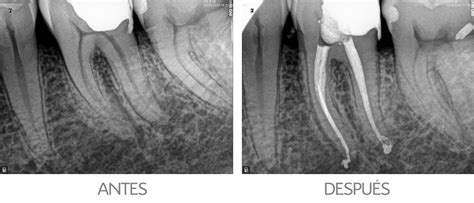

¿Qué es una Endodoncia?

La endodoncia, también conocida como tratamiento de conducto, es un procedimiento que consiste en la eliminación de la pulpa dental inflamada o infectada. Esta pulpa, que está compuesta por nervios y vasos sanguíneos, se encuentra en el interior del diente, específicamente en el conducto radicular. Si estás experimentando dolor dental o sospechas de una infección en la raíz, es fundamental acudir a un especialista cuanto antes.